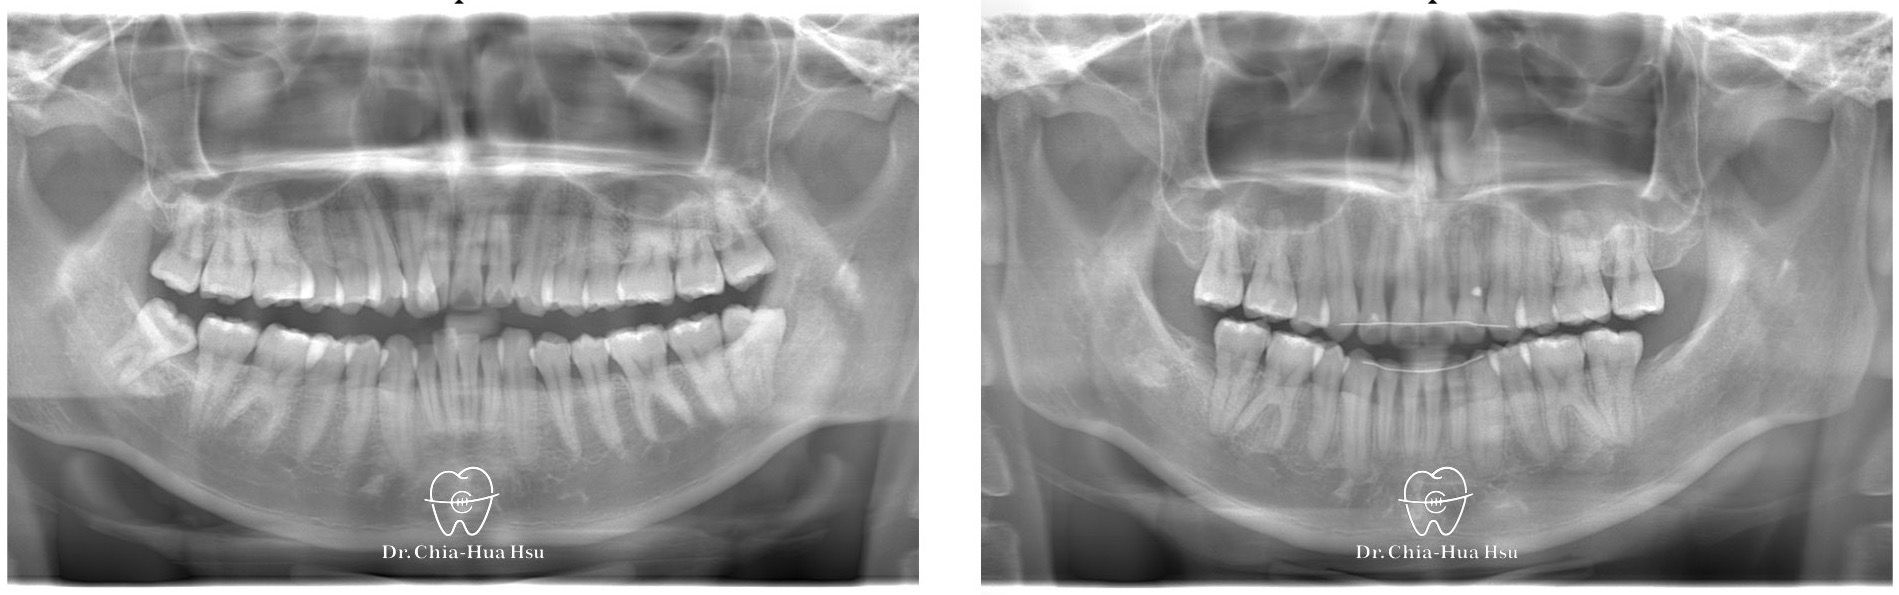

- 治療方式:使用傳統金屬矯正器,拔除四顆小臼齒獲得空間,搭配二級橡皮筋牽引(Class II elastics)。

治療前

治療後

- 治療過程:治療過程中,上顎使用關閉型矯正彈簧(close coil spring),而下顎使用透明橡皮鏈(power chain),來將拔牙空間關閉。